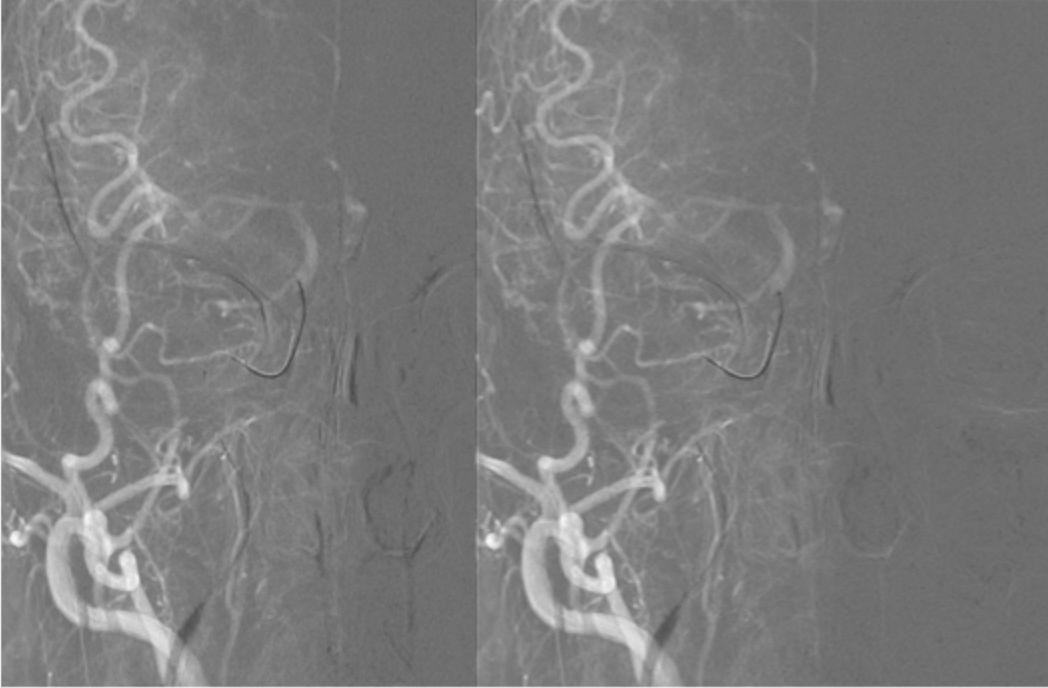

常规消毒铺巾,右侧股动脉穿刺成功,置入9F动脉鞘。150 cm超滑泥鳅导丝携5F单弯造影管分别行双侧颈总、左侧椎动脉正侧位造影,结果显示右侧颈内动脉C1-C4段闭塞,右侧颈外动脉侧枝向右侧眼动脉代偿供血,并反流至右侧颈内动脉颅内段,右侧大脑中、前动脉显影变淡(图5)。14∶50肝素4 000单位入壶,在长交换260 cm泥鳅导丝导引下将MOMA先端置于右侧颈外动脉,撤出泥鳅导丝。路径图下,PILOT50微导丝(0.014"x190 cm)携带Headway 21微导管沿MOMA送入右侧颈内动脉,微导丝通过闭塞段,微导管通过困难(图6)。

图5

图6